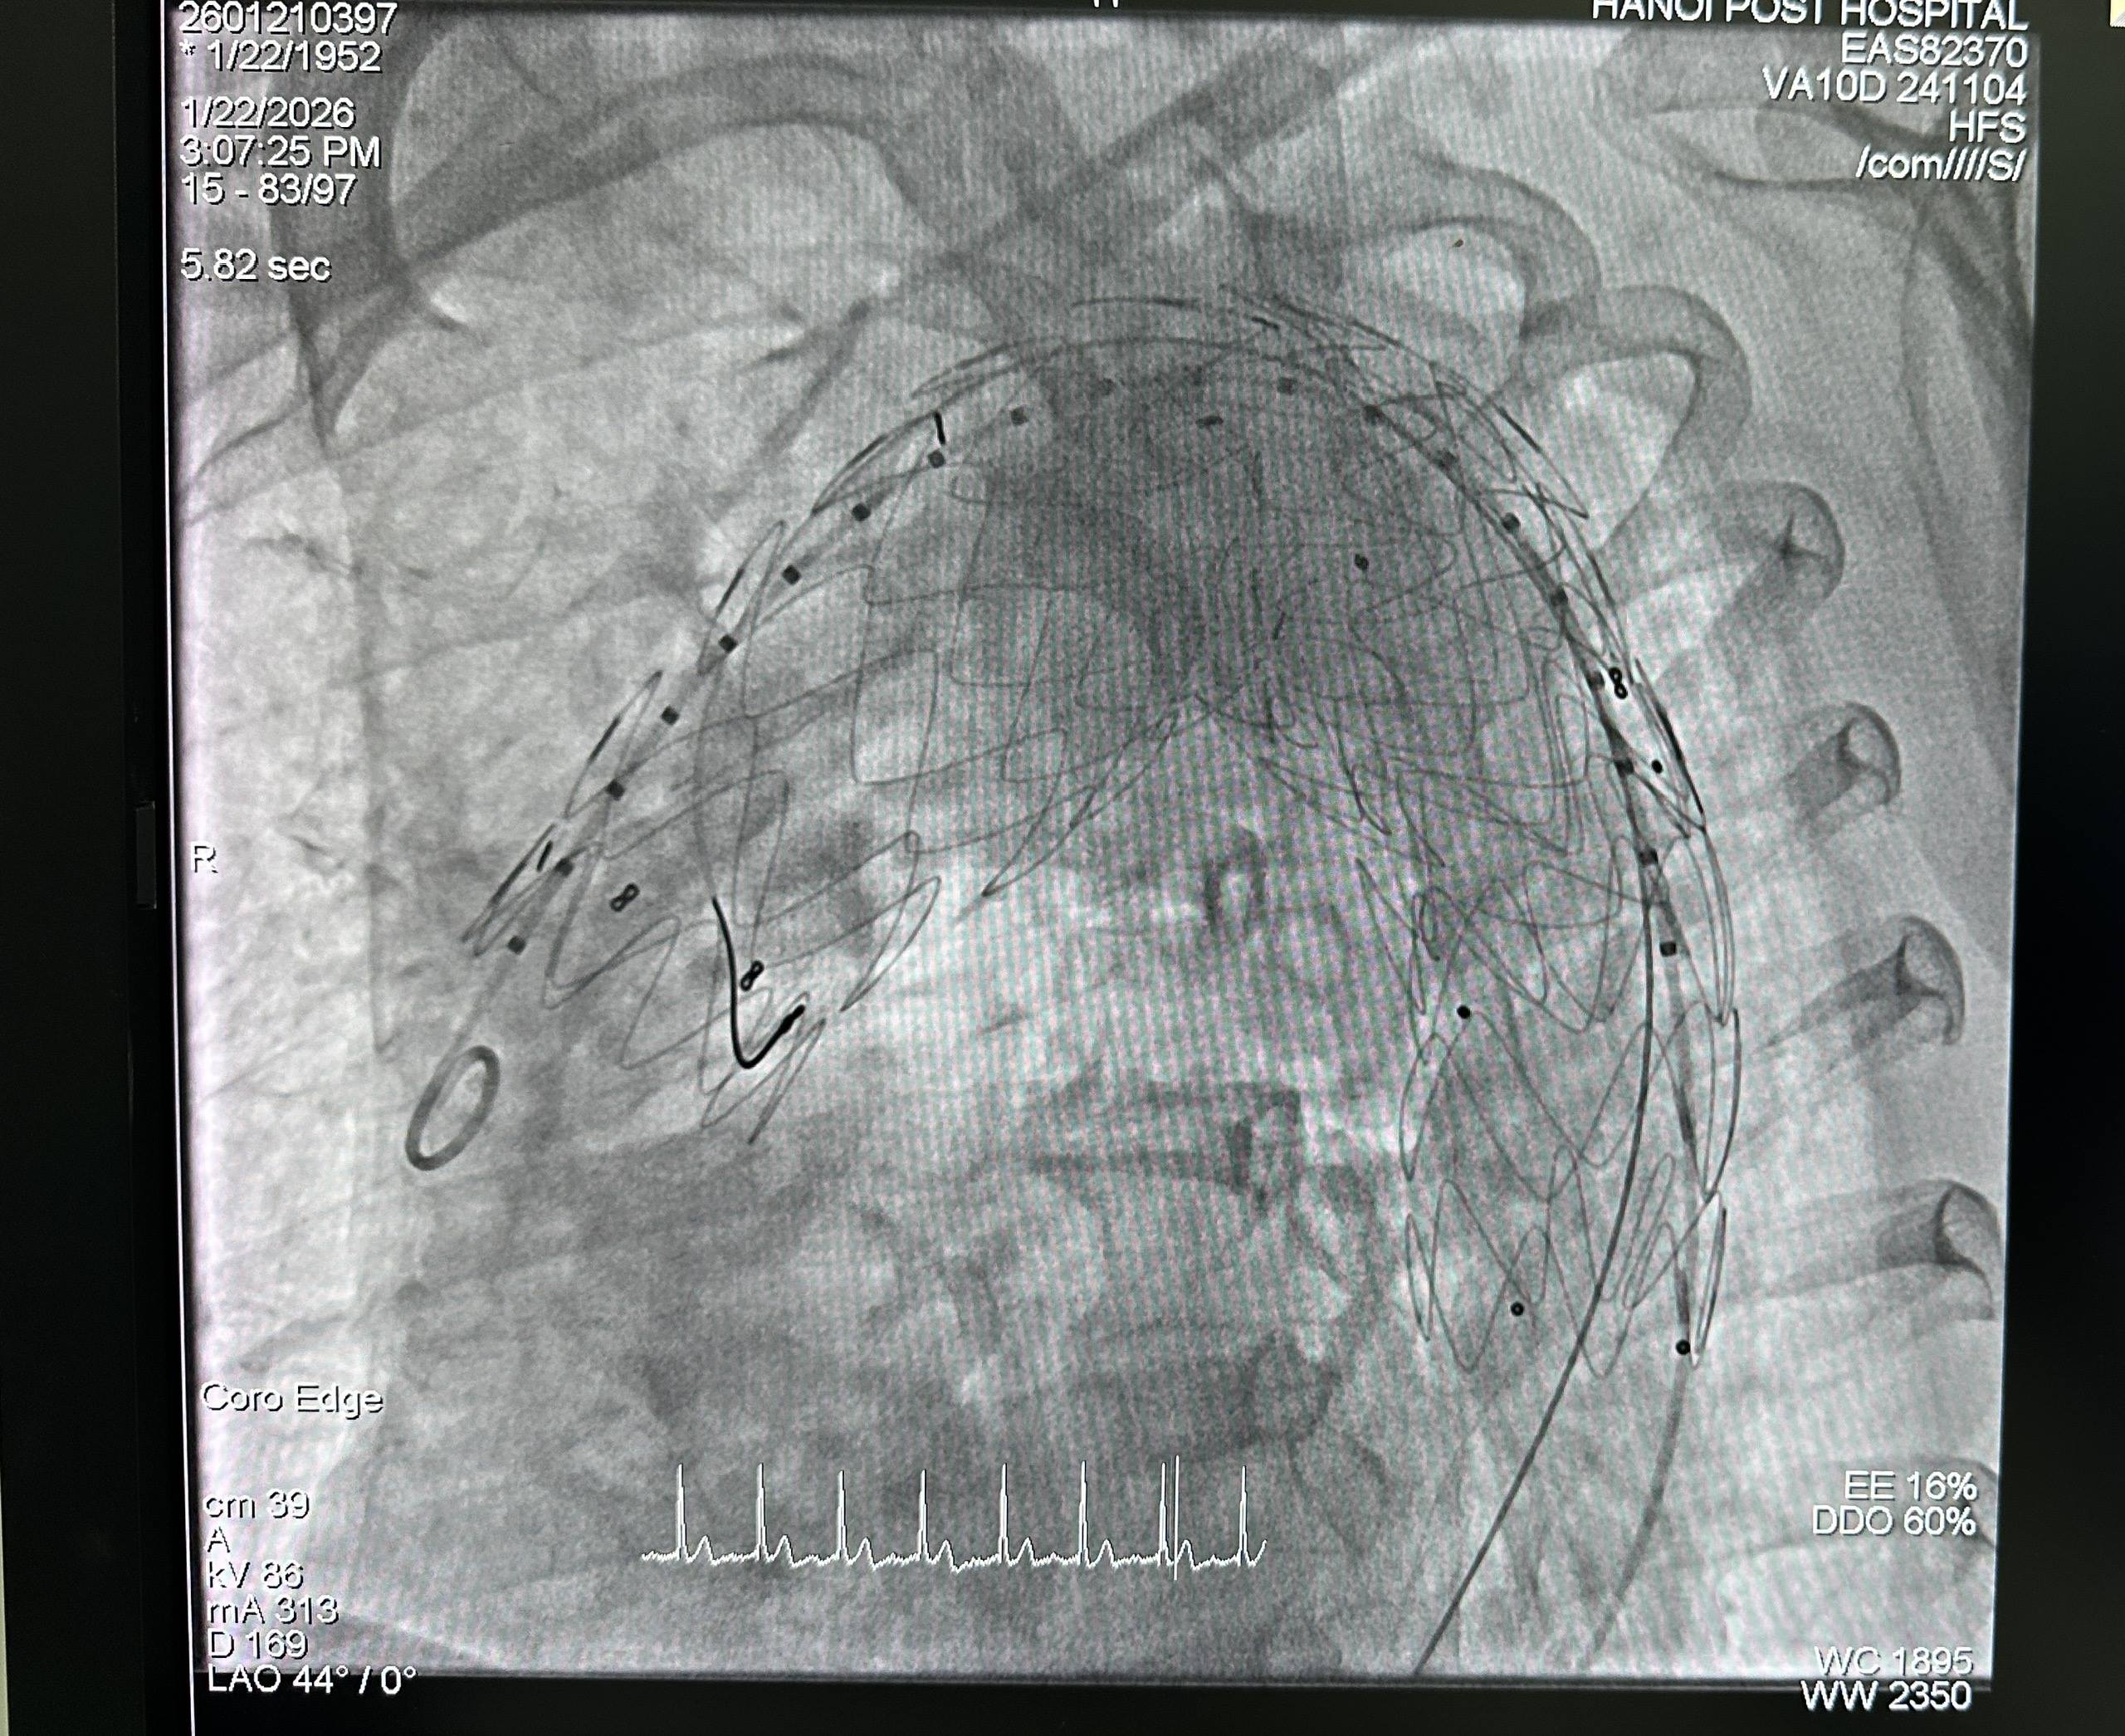

Sau hội chẩn chuyên môn và đánh giá toàn diện bệnh lý nền, thể trạng người bệnh cũng như nguy cơ phẫu thuật, ê-kíp thống nhất lựa chọn phương pháp đặt stent graft nội mạch. Phương pháp này hạn chế xâm lấn, thường không cần gây mê toàn thân, giúp giảm nguy cơ biến chứng và đặc biệt phù hợp với người bệnh cao tuổi có nhiều bệnh lý mạn tính kèm theo. Trong quá trình can thiệp, dưới hướng dẫn hình ảnh DSA, ê-kíp định vị chính xác vị trí túi phình và triển khai stent graft an toàn. Stent graft che phủ hoàn toàn túi phình, tái lập dòng chảy qua động mạch chủ, qua đó phòng ngừa nguy cơ vỡ phình—một biến chứng có thể đe doạ tính mạng. Toàn bộ thủ thuật diễn ra thuận lợi; người bệnh tỉnh táo, các chỉ số sinh tồn được theo dõi liên tục bằng hệ thống monitoring.

Sau can thiệp, tình trạng đau ngực và khó thở của ông C. cải thiện rõ rệt; các chỉ số sinh tồn ổn định. Người bệnh nhanh chóng hồi phục, sớm có thể vận động nhẹ và sinh hoạt trở lại. Kết quả kiểm tra sau can thiệp ghi nhận stent graft hoạt động ổn định, chưa phát hiện biến chứng, cho thấy hiệu quả và tính an toàn của phương pháp.